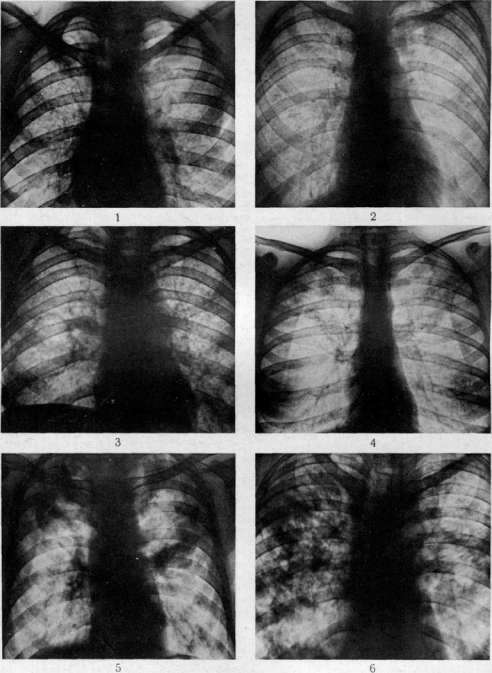

гематогенной генерализацией в результате проникания туб. бацил в ток крови непосредственно или через посредство лимфы (см. Туберкулез). В легких гематогенное поражение проявляется разно. При обшем милиарном Т. в обоих легких наблюдается высыпь массы милиарных туберкулов [см. отд. табл. (ст. 119—120), рис. 3]; в этих случаях ткань легких представляется полнокровной и на таком фоне видны бугорки в зависимости от возраста и типа их или мелкие, серые, полупрозрачные или желтые, с неровными контурами, часто более крупные. Нередко можно, согласно указанию Рибберта (1902), заметить, что у взрослых в верхних районах легких бугорки несколько более крупны, чем в нижних, что объясняют более энергичным ростом туберкулов именно в верхних отделах легких. Если проникание туб. бацил произошло в ветвь легочной артерии, то мидиариза-ция захватывает лишь соответствующую часть легочной территории. Микроскоп, исследование при милиаризации в легких может открыть разный тип бугорков: иногда это типичные продуктивные эпителиоидные бугорки, имеющие своим источником развития альвеолярные перегородки; бугорки растут, сдавливая и уничтожая альвеолы и оставаясь долго продуктивными бугорками; в других случаях к бугорку, начавшему развиваться в альвеолярной перегородке, быстро присоединяется эксудация в альвеолы; наконец бывает так, что бугорок как бы сразу возникает в виде милиарной пневмонии, захватывающей 2—4 соседних альвеолы (милиарный альвеолит), и таким образом обнаруживает экеудативный характер. Гюбшман и Шлейсинг выдвигают ту точку зрения, что всякий бугорок в легких начинается в виде милиарной пневмонии и уже потом окружается продуктивной зоной. Эта точка зрения вызвала категорические возражения крупнейших патологов (Герксгеймер, Ашоф, Штернберг и др.); кроме того Гретман (Grethmann, 1928) установил, что гематогенные милиарные бугорки в легких как правило развиваются в виде продуктивных бугорков из стенок мелких сосудов; эксудация в альвеолы есть явление последовательное, частое, но не обязательное. Гематогенное метастазирование в легкие может еще происходить в виде появления в легких одного или нескольких туб. очагов; по своему существу такая форма есть частное проявление органного T.j возникающего в порядке поздней генерализации первичного Т. (см. Туберкулез). Судьба и выражение таких отдельных гематогенных фокусов в легких бывает разной (см. ниже). Попытка Симона (Simon) объяснить все верхушечные рубцы, встречаемые в легких взрослых, гематогенным метастазированием, происходящим в детстве, у патологов не имела успеха; такое гематогенное метастазирование в верхушку легкого в детском возрасте встречается редко и на детских трупах мы не встречаем ничего похожего на начало образования этих очагов; верхушечные рубцы легких наблюдаются почти только у взрослых, и частота их возрастает с возрастом. Первичный Т. приводит к смерти детей или в связи с значительным распространением туб. процесса в легких или в связи с генерализацией, особенно в виде общего милиарного Т. и туб. менингита, У взрослых первичный Т. легких бывает очень редко; чаще всего это касается тех народностей, к-рые в детском возрасте не соприкасаются с туб. вирусом (см. Туберкулез).—В торичный Т. легких представляет собой то, что принято выделять в качестве легочной чахотки взрослых; по существу это—вспышка туб. процесса, или реинфект в легком у индивидуума, к-рый уже перенес первичную инфекцию и является относительно иммунным к туб. вирусу. Главной особенностью вторичного Т., или реинфекта является то, что процесс протекает б. или м. изолированно в легком, не обнаруживая склонности к лимфогенным и гематогенным метастазам. Если пат. анатомия легочной чахотки взрослых уже давно разработана достаточно хорошо и представляется б. или м. ясной, то этого нельзя сказать относительно патогенеза начальных изменений. В прежнее время, когда еще не делалось различий между Т. детского возраста и Т. взрослых, когда еще не было ничего известно по поводу первичного и вторичного Т., аллергии и пр., казались совершенно очевидными два обстоятельства: 1) легочная чахотка взрослых есть следствие аэрогенной инфекции легкого туб. палочкой; 2) легочная чахотка взрослых всегда начинается в области верхушки легкого. Изучение строения начальных фокусов Т., обнаруживаемых в верхушках, показало (Birch-Hirschfeld,1899; Schmorl,1901), что в них дело идет о туб. поражении стенки апикального бронха и развитии в таком месте бронхита с перибронхитом. Абрикосов (1904) при своих исследованиях начальных туб. очагов верхушек пришел к несколько иному заключению; он нашел, что поражение обычно начинается ниже, именно в районе 2-го дорсального субапикального бронха верхней доли и что фокус имеет бронхопневмонический характер. Абрикосов высказался за то, что процесс начинается со стенки внутридольковой бронхиолы и быстро принимает бронхопневмонический характер. Эти исследования подвели как бы фактический фундамент под теорию аэрогенного происхождения легочной чахотки; отчасти в связи с этим взгляды Ауфрехта (Aufrecht, 1900) и Рибберта (1901) о гематогенном происхождении легочного Т. взрослых не имели никакого успеха. После того как выдвинулось положение о патогенетическом отличии Т. детского возраста и Т. взрослых и сущность этого отличия была разъяснена в учении Ранке (см. Туберкулез), стало очевидным, что так просто смотреть на генез легочной чахотки взрослых, как это делалось раньше, нельзя. Раз оказалось, что легочная чахотка взрослых есть Т. организма, уже перенесшего туб. инфекцию, то естественно стали говорить, что в основе Т. взрослых лежит вторая инфекция, или реинфекция туб. вирусом. Механизм этой реинфекции понимался различно. По учению Ранке, реинфекция представляет собой не что иное, как обострение-изменений, относящихся к первичному Т. детского возраста (эндогенная реинфекция); т. о. Т. взрослых есть продолжение Т., идущего с детского возраста, но обостряющегося у взрослого, находящегося в состоянии относительного иммунитета к туб. вирусу. В противоположность этому Ашоф и др. стали настаивать на том, что легочная чахотка взрослых в громадном большинстве случаев есть следствие новой аэрогенной инфекции легкого, т. е.— экзогенная реинфекция или суперинфекция организма, уже перенесшего первичную.инфекцию. В последние годы очень многие фтизиатры склонились к мнению, что легочная ча- хотка взрослых есть следствие эндогенной реин-фекции по гематогенному пути. Источником такого гематогенного метастазирования в легкое являются или очаги первичного комплекса в легком и в лимф, железе средостения или туб. фокус в каком-нибудь органе, развившийся в порядке органного туберкулеза. Другой спорный пункт, выявившийся в последние годы, касается места начала легочной чахотки взрослых. До 1925 г. учение о том, что легочная чахотка начинается с самой верхушки легкого к что встречающиеся в верхушках рубцы с петрификатами и без них являются как раз выражением такого начала, не получившего в дальнейшем развития (зажившие очаги реинфекта), казалось совершенно незыблемым. В 1925 г. Асман (Assmann), в 1926 г. Редекер (Redeker), а в ближайшее время Ульрици, Ромберг, Лидтин (Romberg, Lydtin) и мн. др. на основании клинических и рентгенологических данных стали настаивать на том, что вышеуказанные верхушечные очаги никакого отношения к началу легочной чахотки не имеют, что легочная чахотка начинается не в верхушке, а в той области верхней доли, к-рая проецируется непосредственно ниже ключицы; как раз здесь начинается процесс в виде очага пневмонии, что и было обозначено как и н -ф р а к л а в и к у л я р н ы й (подключичный) инфил ьтрат или ранний ту б. инфильтрат (нем. Fruhinfiltrat). С такой точкой зрения не могли согласиться патологоанатомы (Ашоф, Graff, Гюбшман, Loeschke и др.), которые утверждали, что инфракдавикудярный инфильтрат не есть анат. начало легочной чахотки, а лишь клинико-рентгенологическое выявление процесса, начавшегося в верхушке и протекавшего до того без ясных клин, симптомов. На специальном туб. конгрессе в Вильд-баде (1928) и на съезде патологов в Вене (1929) это противоречие еще не было устранено. Однако в самое последнее время мы видим значительное смягчение указанного спора, связанное с тем обстоятельством, что, с одной стороны, патологоанатомы (Ашоф, Штернберг, Pa-gel, Schtirmann и др.) склонились к допущению возможности начала туб. процесса у взрослых с подключичной области, а с другой стороны, и клиницисты (Лидтин, Асман, Star linger, Рубинштейн и др.) согласились с тем, что инфракдавикулярный инфильтрат вовсе не обязательно является самостоятельным начальным фокусом Т., он может развиваться и последовательно из предсуществовавшего лятентного очага. Одновременно стали определенно говорить, что реинфект, являющийся началом легочной чахотки взрослых, может иметь как эндогенное, так и экзогенное происхождение. Т. о. в наст, время допускаются разные способы происхождения легочной чахотки взрослых и разные типы ее начала. Происхождение ее может быть в результате экзогенной (аэрогенной) и эндогенной реинфекции; эндогенная реинфекция развивается гематогенно или непосредственно из старого очага в легком (по соприкосновению иди бронхогенно). В смысле своего начала процесс может исходить из верхушечных очагов иди начаться в подключичной области. К этому надо еще прибавить возможность развития легочной чахотки взрослых из туб. лимф, желез ворот легкого. Последний способ образования реинфекта в легком является однако сравнительно редким; поэтому практическое значение имеют два спо- соба начала легочной чахотки: из верхушки легкого и из подключичной области его. С этим в наст, время согласно большинство патологов и клиницистов (Ашоф, Pagel, Schilrmann, Асман, Лидтин, Рубинштейн, Угрюмов, Штеф-ко и др.). Однако нет еще полного согласия в том, какой способ начала является более частым; у клиницистов имеется склонность считать инфраклавикулярное начало более обычным и указывать, что верхушечное начало наблюдается, лишь в 7—1Q% случаев Т. (Ромберг). С другой стороны, патологоанатомы на основании секционного материала устанавливают, что случаи с верхушечным началом относятся к случаям с подключичным началом, как 4 : 1 (Pagel, Угрюмов), т. е., что начало с верхушки легкого в 4 раза чаще, чем начало с инфракла-викулярной области. Совершенно открытым считается вопрос о том, насколько часто аэрогенное (экзогенное) и насколько часто гематогенное (а также другого типа эндогенаое) развитие реинфекта. Большинство указывает, что инфракдавикудярный очаг имеет гематогенное происхождение, тогда как верхушечные очаги могут иметь аэрогенное и гематогенное происхождение. В противоположность этому Нейман и Штарлингер (Neumann, Star linger) считают, что как раз ранний инфракдавикудярный инфильтрат есть результат аэрогенной (бронхогенной) суперинфекции, тогда как верхушечные очаги имеют гл. обр. гематогенное происхождение. Оставляя в стороне эти еще неясные и спорные пункты генеза легочной чахотки, коснемся пат. анатомии: 1) верхушечных очагов и 2) ин-фраклавикулярных инфильтратов. 1. Понятие «верхушка легкого» не у всех авторов одинаково; одни под «верхушкой» понимают лишь самый купол верхушки (нем. Кирре), другие—верхнюю треть верхней доли. Разное понимание является одной из причин несогласного толкования у авторов локализации верхушечных очагов. Надо заметить, что у взрослых предрасположенной к Т. является вся верхняя треть верхней доли легкого, в к-рой и встречаются верхушечные очаги реинфекта. Предрасположение этой верхней части легкого к Т. по современным воззрениям (Ors6s, Loeschke) связано с тем, что на ней наиболее сильно сказывается влияние тяги диафрагмы, создающей здесь малокровие и ателектатическое состояние легочной ткани вследствие сдавления сосудов и бронхов; это проявляется особенно сильно у лиц с астенической грудной клеткой. Относительно числа и локализации верхушечных реинфектов наиболее точные данные представляются Шюрма-ном: в 40,8% всех реинфектов обнаружен 1 очаг, в 26,4%—2—4 очага, в 23,2%—5—10 очагов, в 9,6%—более 10 очагов. Множественные реин-фекты могут иметь одинаковый возраст, что говорит за одновременное их образование, или же представляют разную степень развития, что свидетельствует о разном сроке их возникновения и м. б. зависимости друг от друга. В 37,4% реинфекты имелись только в правом легком, в 30,1% — только в левом, в 32,5%—в обоих легких. В 40% очаги лежали в самом куполе верхушки, в 60% пальца на два ниже купола (Абрикосов также находил, что начальные очаги обычно лежат не в самом куполе, а в районе субапикального бронха). По Стру-кову 00,4% очагов встречаются в правом легком, 23,2%—в левом, 16,4%—в обоих легких. Х17 Внешний вид верхушечных очагов может быть разным. Размеры их колеблются от 2 до 15 мм в диаметре. Иногда очаг представляет собой просто ограниченное утолщение плевры, на разрезе к-рого обнаруживается слой плотной хрящеподобной соединительной ткани без каких-либо творожистых гнезд и петрификатов, в других случаях это — антракотический очаг, тоже располагающийся плеврально, далее идут втянутые рубцы, связанные с плеврой и сопровождающиеся образованием синехий между париетальной и висцеральной плеврой; они могут быть без петрификатов или с ними; наконец часто встречаются казеозные и петри-фицированные очаги, расположенные в отдалении от поверхности и находящиеся в связи с плеврой или лежащие свободно в легочной ткани без связи с плеврой. Имеется склонность (Штефко) подразделять эти очаги на: 1) интра-пульмоналыгые и 2) плевропулъмональные (экстрапудьмональные, плевральные) с подразделением интрапульмональных очагов (Стру-ков) на: а) классические верхушечные реинфек-ты(аэрогенные) и б) очаги Пуля (гематогенные). Другие, выключая плевральные очаги как не-слецифические, рассматривают отдельно Симоновские и Пулевские очаги и т. д. Описания этих отдельных типов верхушечных очагов и их квалификация далеко не совпадают у разных авторов, что заставляет считать вышеуказанные классификации, точно так же как определение одних очагов как гематогенных, других—как аэрогенных, весьма субъективными и шаткими. Если плевральные утолщения и антракотические узелки без казеоза и петрификатов не считать относящимися к Т., то получается, что реинфекты встречаются в 50— 60% всех трупов взрослых; если же квалифицировать как tbc также и плевральные утолщения, рубчики, антракотические узелкрг (как это делают Ашоф, Focke, Anders и др.), то оказывается, что очаги реинфекта встречаются на трупах взрослых не реже, чем первичный аффект, т. е. в 95—98%. По современным воззрениям всякий реин-фект в самом начале его развития представляется в виде очага «раннего инфильтрата», т. е. пневмонического фокуса с весьма слабыми про-лиферативными явлениями; это конечно еще не исключает того, что и до вспышки пневмонического процесса в стенке бронхиолы имелся туб. очажок, к-рый и является началом всего процесса. Очаг пневмонии может подвергнуться обратному развитию, рассасыванию, чаще однако он претерпевает творожистое перерождение и инкапсуляцию. Инкапсулированные очаги реинфекта, Пулевские или Ашоф-Пулев-ские очаги, как их называют (в противоположность Гоновским очагам первичного аффекта), очень полиморфны по своему виду; они то круглы, то овальны, то состоят из группы отдельных узелков, нередко ориентированных по разветвлениям мелкого бронха; особенностью их является нерезко выраженная и сравнительно поздняя петрификация, отсутствие образования в капсуле костной ткани, толстая неспецифическая капсула с углем и с распространением соединительнотканного разрастания с лимфоидными скоплениями на соседнюю легочную ткань; нередко образование соединительнотканных тяжей, связывающих капсулу с плеврой, с сосудами и бронхами. Иногда вокруг очага легочная ткань па большом протяжении ателектатична, склерозирована, ан- тракотична, с бронхоэктазами. Как показывает бактериол. исследование инкапсулированных и петрифицированных очагов реинфекта, в них долго содержатся вирулентные туб. бацилы. Кроме того и микроскоп, исследование нередко вокруг таких казалось бы совершенно заживших очагов открывает свежие бугорки. Поражения регионарных лимф, желез при реинфек-тах не бывает; иногда в железах наблюдаются лишь отдельные бугорки. Как уже указано, в наст, время взгляд, что верхушечные реинфекты могут быть источником легочной чахотки, т. е. прогрессирующего Т., является общепринятым. Развитие туб. процесса из верхушечных очагов происходит 4 способами: 1) иногда образовавшийся реинфект непосредственно увеличивается и образует крупный пневмонический очаг (верхушечный инфильтрат), к-рый в дальнейшем прогрессирует; 2) в других случаях рядом с как бы зажившим реинфектом по соприкосновению появляются свежие бугорки и очаги пневмонического типа; 3) очаг реинфекта, расположенный у стенки бронха, дает прорыв в бронх и развитие бронхогенных метастазов как вблизи, так и в отдалении от очага; 4) из реинфекта процесс распространяется лим-фогенно по ходу бронха, давая туб. периброн-хит, а в дальнейшем и туб. бронхит с бронхо-гешгой диссеминацией. Лешке считает эти два последних пути самыми частыми типами начала легочной чахотки взрослых и даже инфракла-викулярный инфильтрат квалифицирует как бронхогенный метастаз из верхушечного реинфекта. 2. Инфраклавикулярный ранний инфильтрат с патологоанатомической стороны описан небольшим числом авторов (Асман, Zadek, Schurmann, Pagel, Штефко, Рубинштейн и Пожариский, Угрюмо в); зависит это от того, что в периоде раннего инфильтрата больные не умирают, вследствие чего ранний инфильтрат в большинстве случаев можно уловить на секционном столе лишь в качестве случайной находки у б-ных, умерших от других б-ней. Анатомически инфраклавикулярный инфильтрат представляет очаг острой се-розно-фибринозной пневмонии с колятераль-ным отеком; такой очаг может в дальнейшем рассосаться, оставив после себя лишь небольшой склероз легочной ткани, или же подвергается творожистому перерождению, представляя в этом случае однородное казеозное поле величиной в 2—3 см в диаметре; казеозный очаг может инкапсулироваться и петрифициро-ваться; однако нередко происходит размягчение творожистой массы и выделение распада через бронх, что ведет к образованию полости с казеозными изрытыми стенками, называемой ранней каверной. По периферии основного очага инфильтрата нередко наблюдается ряд более мелких очагов такого же строения и с тем же течением. Распад очага и сообщение его с бронхом являются предпосылкой к прогрессирующему распространению Т., т. е. развитию легочной чахотки. Происхождение ин-фраклавикулярных инфильтратов повидимому не всегда бывает одинаковым. Нет никакого сомнения в том, что они могут возникать как самостоятельный реинфект, вероятно гематогенного (по Штарлингеру—аэрогенного) происхождения; с другой стороны, нельзя отрицать возможности развития их из более старых реинфектов, к-рые могут располагаться вблизи инфраклавикудярного района (Абрикосов, Шюрман, Ашоф), или даже из верхушечных ре-инфектов в духе взгляда Лешке. Указывается еще возможность образования инфраклавику-лярных инфильтратов по ретроградному току лимфы из бронхиальных лимф, желез, пораженных Т. Если инфраклавикулярный инфильтрат может иметь разное происхождение, то естественно возникает мысль о том, что подключичная область легкого представляется особо предрасположенной к вспышке здесь туб. пневмонии при разных путях проникновения туб. вируса. Более редкими типами начала легочной чахотки надо считать следующие. 3. Многие выделяют еще в качестве особого вида начальных изменений при легочной чахотке гематогенную форму начала. В качестве признаков этой формы, кроме наличия где-нибудь в организме очага, могущего дать гематогенные метастазы, указываются: множественные, равномерно распределенные в верхушке легкого мелкие фокусы или множественные небольшие однородные каверны среди ин-дурированной иди эмфизематозной ткани; эти очаги обладают сравнительно небольшой наклонностью к распространению, особенно брон-хогенному. 4. Реинфект из туб. лимфатических желез ворот легких происходит в тех случаях, когда после ликвидации первичного аффекта в легком процесс в регионарной лимф, железе или в группе желез продолжает существовать в лятентном состоянии; в легком в таких случаях может вспыхнуть процесс по соприкосновению непосредственно в примыкающей легочной ткани в виде гилюсного инфильтрата, или же происходит ретроградное распространение внутрь легкого по лимф, путям, или наконец процесс с лимф, железы переходит на стенку бронха и дает бронхогенные метастазы, как это бывает в периоде первичного туберкулеза. Процесс, начавшийся по одному из вышеуказанных четырех способов (чаще по способу 1 или 2), распространяется частью по соприкосновению, частью по воздухоносным путям легкого, т. е. интраканаликулярно, бронхогенно. Как правило при легочной чахотке взрослых распространение туб. процесса, начавшегося в верхнем отделе легкого, идет в направлении сверху вниз; поэтому в верхних отделах имеются более старые изменения и, чем ниже, тем изменения являются более свежими. Характер всех этих изменений соответствует тому, что указано выше о пат. анатомии Т. вообще (см. Туберкулез). Распространение из места начала процесса по соприкосновению выражается или в том, что зона пневмонических (эксудативных) изменений быстро расширяется, подвергается казеозу, распаду [см. отд. табл. (ст. 119—120), рис. 4, и отд. табл. (ст. 111—112), рис. 5] с образованием одной или нескольких полостей—каверн (см.), или, если первоначальный очаг был окружен зоной специфической грануляционной ткани и бугорками, происходит преимущественно продуктивное, сравнительно медленное разрастание этой грануляционной ткани и развитие новых бугорков с сдавливанием и уничтожением альвеол и слабыми пневмоническими (эксудативными) проявлениями. В дальнейшем указанные грануляционные разрастания [см. отд. табл. (ст. 35— 36), рис. 1] могут подвергнуться казеозу, распаду или же обнаруживают склонность к фиброзному превращению, сопровождаясь неред- ко развитием вокруг неспецифической соединительной ткани. Бронхогенное распространение при легочной чахотке взрослых имеет доминирующее значение. При нарушении целости бронха в районе начального фокуса или в связи с уже имеющимся сообщением с просветом бронха в виду бронхопневмонического строения очага творожистые массы, содержащие туб. ба-цилы, при дыхательных движениях передвигаются в просвете бронха и аспирационно заносятся в новые разветвления бронхиального дерева. В результате заноса инфекционного материала в мелкие бронхи—бронхиолы—вспыхивают преимущественно эксудативные очаги туб. пневмонии, соответствующие той части дольки, к-рая носит название ацинуса; их называют ацинозными очагами; они имеют вид желтовато-серых, угловатых очагов размерами ок. 2 лиц в диаметре («мелкое зерно» рентгенологов). Аци-нозный фокус, имея вначале пневмонический характер, может в дальнейшем сохранять таковой и увеличиваться, захватывая соседние ацинусы и давая в конце-концов более крупный лобулярный (дольковый) пневмонический фокус. Лобулярный фокус может образоваться и сразу как таковой при распределении инфекционного материала сразу по всем ветвям лобулярного бронха. Лобулярный очаг имеет вид казеозного фокуса с фестончатым краем; размер его около 1,5 см в диаметре («крупное зерно» рентгенологов). С другой стороны, ацинозный очаг может в самом начале получить грануляционную зону, ограничивающую его распространение и придающую ему преимущественно продуктивный характер. Группа рядом расположенных таких ациноз-ных очагов с продуктивной зоной дает т. н. ацинозно-нодозный фокус [см. отд. табл. (ст. 119—120), рис. 1, верхушка легкого— см. нижнюю часть рисунка]; обычно фокус име-ет центральную часть, состоящую из ателек-татической, богатой угольным пигментом легочной ткани, и периферию из ряда продуктивных ацинозных очагов; размер ацинозно-но-дозного фокуса около 1,5 &м в диаметре («крупное зерно» рентгенологов). Как дольковые пневмонические, так и ацинозно-нодозные фокусы могут сливаться друг с другом, в результате чего образуются поля разных размеров эксу-дативного или преимущественно казеозно-пнев-монического характера или преимущественно продуктивные, состоящие из узелков разных размеров, в центре казеоэных, по периферии— грануляционных и нередко даже с фиброзом; Иногда при легочной чахотке происходит вспышка пневмонического процесса, захватывающего сразу целую долю легкого (л о б а р -ная туб. пневмония). В таких случаях вся доля (обычно нижняя) представляется увеличенной, плотной, со стороны плевры серой; на разрезе в начале процесса ткань нижней доли однородно серого вида; под микроскопом картина катарально-фибринозной пневмонии с большим участием пролиферирующих и десква-мирующихся клеток альвеолярного эпителия (по мнению нек-рых исследователей часть этих клеток относится не к эпителию, а к макро-фагам, выходящим из соединительной ткани альвеолярных перегородок). При видном участии в эксудате альвеолярного эпителия говорят о десквамативной, Булевской туб. пневмонии. Есть данные, говорящие за то, что туб. пневмонии, даже лобарные, не подвергаю-

Plic, 1. Линии ню-ипдопииП, uitpcvririeeuiifi Ll>c легкого t клисрнлмн: n ракушке iiv-4 Mkiiujjuii.it творожистые м.-^си. 1'kCf % АщшовошЙ Ll?c легкого. Рис 3. .""■ "i ■ ■ - -1 - - ■ - -iiiji'i Иpc легкого. Рисунок А. Эксчтштирш.ift iEtc нижней доли легкого; hhoiйчн^шние K..ii!--|'FMJ мiiktic11 доли. Рве. ?>. 1к'|'пич1ил1 туб. комплекс: иолп^СЕнтльнми ТВОРОЖИСТЫМ фокус ЛЕГКОГО II pLTHOHil[4INn ЛНМфалеИНТ; МНЛНОрниЧ IOC UOrjHX JWULL